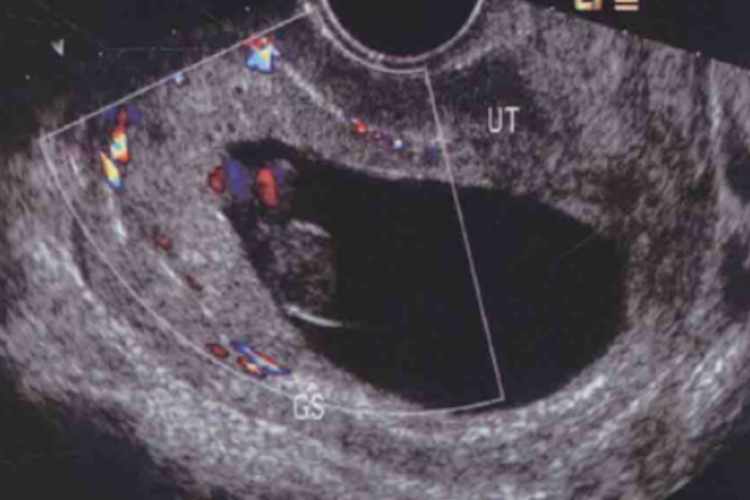

怀孕8周时胎儿初具人形,头大,占整个胎体一半,能分辨出眼、耳、鼻、口,四肢已初具雏形,B超可见早期心脏形成并有搏动。此时胚胎大小约为2cm,尺寸似葡萄大小。